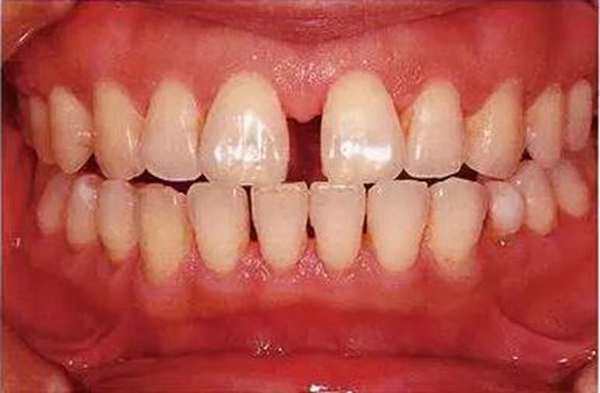

●33歲男性 侵襲性牙周炎廣泛型口腔內(nèi)照片

33歲男性,吸煙(1天10根,12年吸煙史)。菌斑控制狀況不好,牙周探診全頜牙周袋深5~10mm之外,全頜性牙周袋出血,部分牙周袋有排膿現(xiàn)象。X片可觀察到全頜性重度骨吸收。通過(guò)以上檢查可診斷出該患者為侵襲性牙周炎廣泛型。視診可知牙齦雖然有炎癥,但沒(méi)有出現(xiàn)嚴(yán)重浮腫,沒(méi)有大量牙結(jié)石沉積。